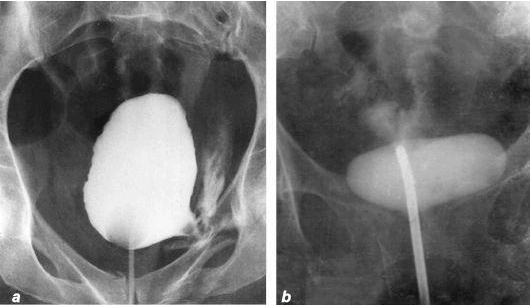

Quiero mostrar algunas fotos de lo que sucede con el sistema genitourinario y otros órganos internos de un hombre cuando deja de tener sexo.

Así es como se ve la inflamación de la próstata debido a la congestión (sin no se vacían los testículos). La inflamación prolongada conduce primero al adenoma y luego al cáncer de próstata (que suele ser fatal). En ausencia de sexo siempre ocurre, por lo que el adenoma se considera una enfermedad de los ancianos.